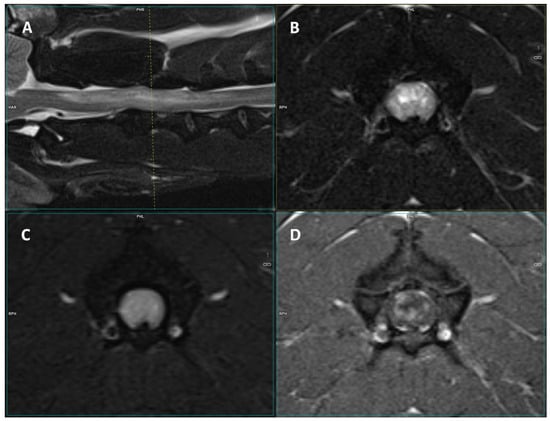

Figure 1.

Images of a 3-T MRI study of a 5-year-old male French Bulldog. (A) Mid-sagittal T2-W, (B) T2-W transverse, (C) FLAIR, and (D) T1 post-contrast transverse images of the cervical spinal cord. At the level of C2–C4, there is a diffuse, cloudy T2-W and FLAIR hyperintensity that displays inhomogeneous contrast enhancement.

The lesions were mostly T2-W hyperintense, FLAIR/STIR hyperintense, and T1-W isointense, showing contrast enhancement (Table 3, Figure 1 and Figure 2). A total of 44.4% (n = 12) of dogs displayed meningeal contrast enhancement.